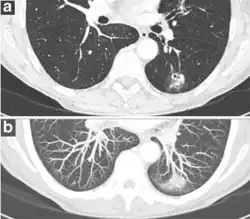

- Pleural retraction is far more common in cancers.[9] It is the pulling of visceral pleura towards the nodule.[9]

-

Nodule with pleural retraction.[9] -

In this case, pleural retraction is seen as a triangular fat component.[9]

- A lung nodule abutting a pulmonary cyst is a rare finding, yet indicating cancer.[9]

- Bubble-like lucencies in the nodule indicate cancer:[9]

- Vascular convergence is where vessels converge to a nodule without adjoining or contacting the edge of the nodule, and is mainly seen in peripheral subsolid lung cancers.[9] It reflects angiogenesis.[9]

Air bronchograms is defined as a pattern of air-filled bronchi on a background of airless lung, and may be seen in both benign and malignant nodules, but certain patterns thereof may help in risk stratification.[9]